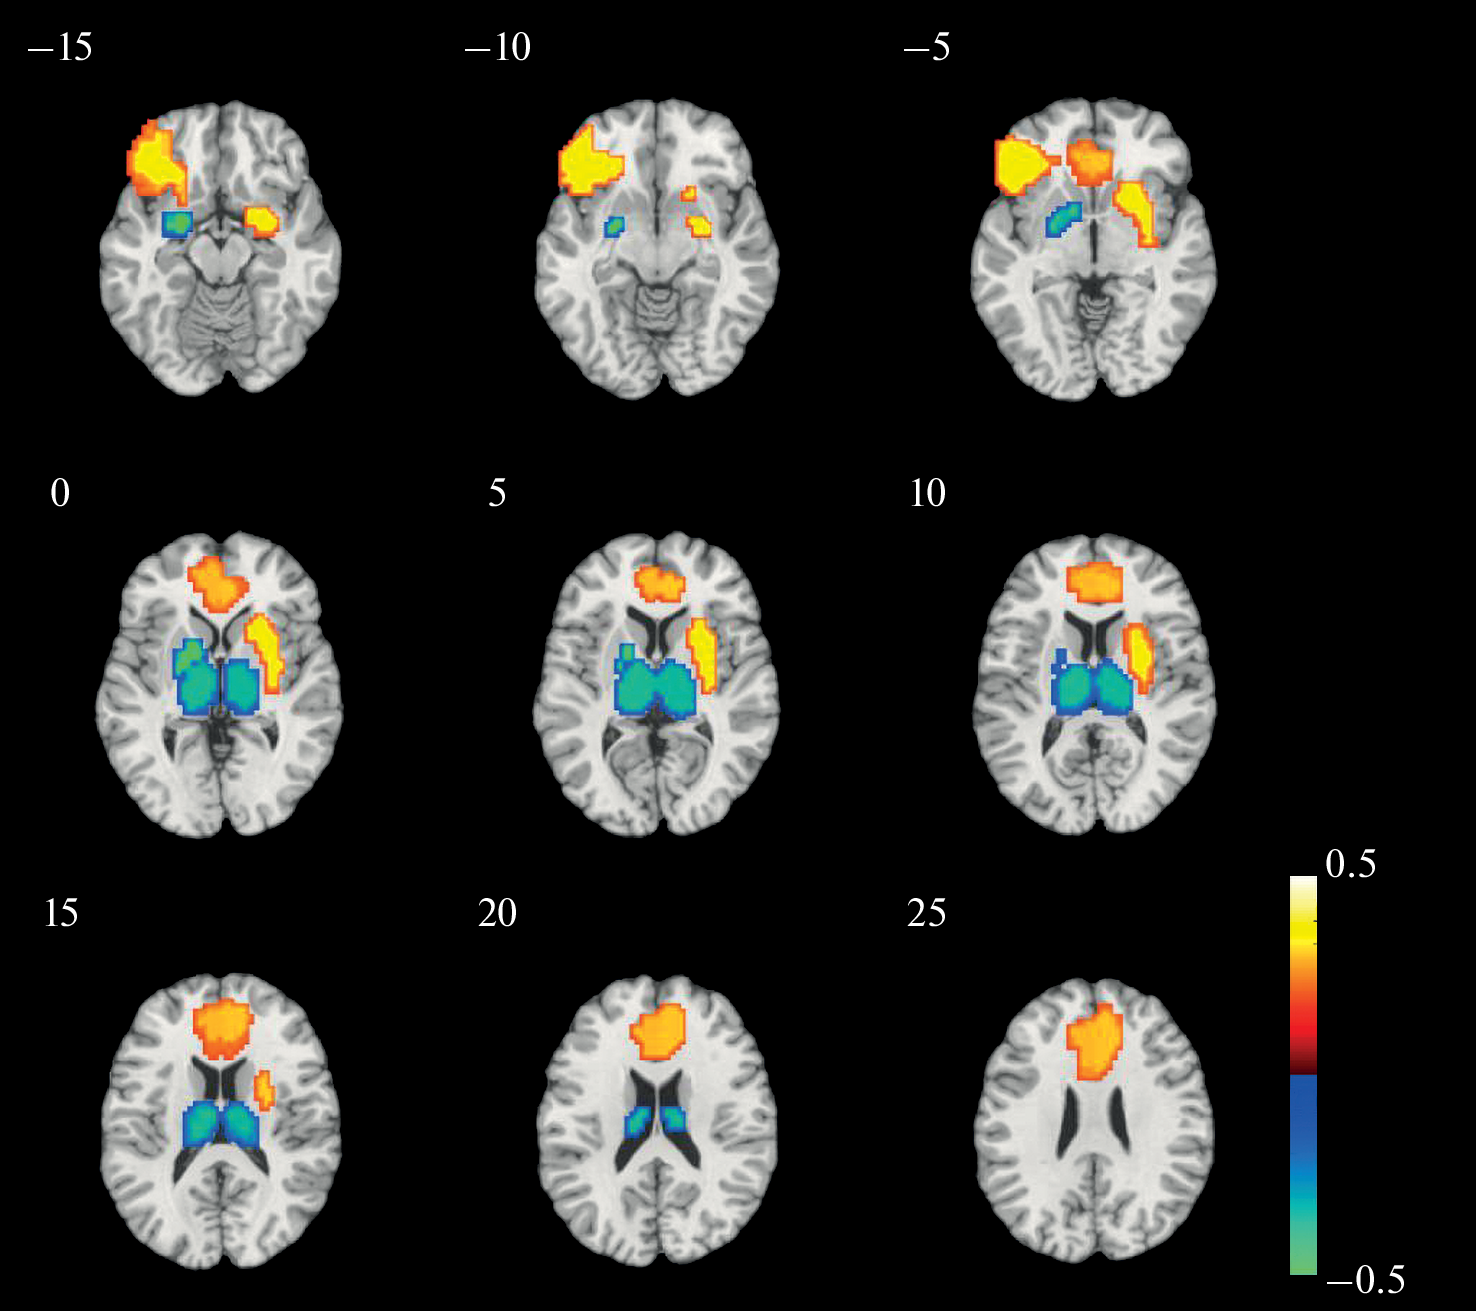

The study of brain activity in the processing of self-referential information, as compared to the processing of information related to other people, is based on the application of mass-univariate analysis, based on the assumption that activity in one region is independent of activity in other regions. Recently, there has been a growing interest in neuroimaging to investigate spatially distributed information using multivariate approaches such as multivoxel pattern analysis (MVPA). In this paper, we used MVPA to analyze fMRI data recorded during self-evaluation and evaluation of other people of varying proximity. In all pairwise classifications tested, the number of correct identifications was significantly higher than the level of random matches. Predictively significant structures were widely distributed over different brain regions and included areas of the visual, lateral prefrontal, and many other cortical areas in addition to the cortical midline structures that contributed the most. In the self-other classification, ventral areas of the medial prefrontal and cingulate cortex were the most informative for the self condition, whereas parietal and occipital medial areas were the most informative for the other condition. The combination of brain structures, which included the anterior cingulate cortex and both amygdalae, revealed by principal component analysis, correlated positively with the psychometric scale of sensitivity to reward, and negatively with neuroticism scales. Overall, the results show the fruitfulness of using machine learning methods to analyze data from such kinds of experiments.